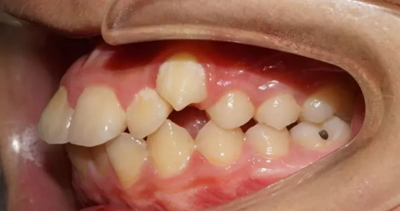

03 牙列擁擠

因虎牙特別突出、牙齒層次不齊前來就診,該如何避免?